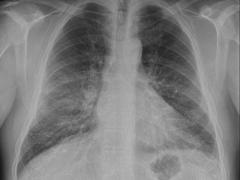

Beoordeling van radiologische beelden